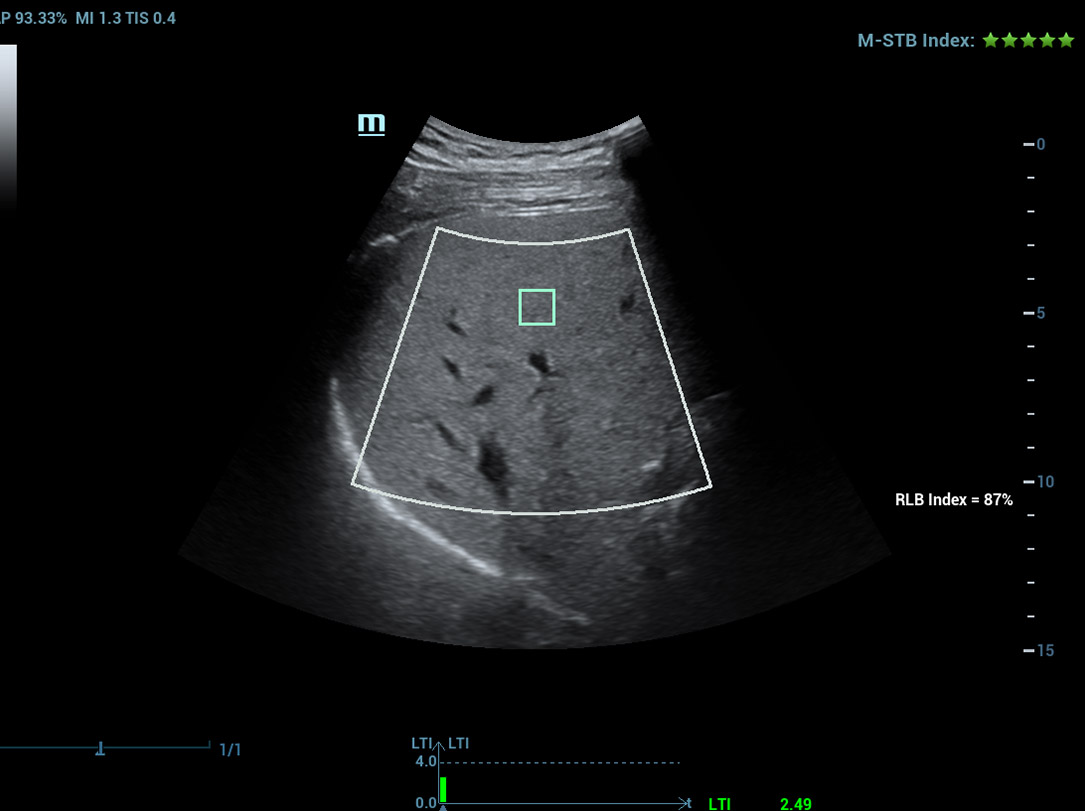

Multi-parametrisch lab voor leververvetting

Een sprong vooruit in het onderzoek naar steatose

Multi-parametrisch lab voor leververvetting

Het multi-parametrische lab voor leververvetting biedt meerdere tools voor kwantitatieve analyse die gebaseerd zijn op verschillende akoestische technologie?n. Het maakt een kwantitatieve analyse van steatose mogelijk en verbetert de gevoeligheid van de detectie van leververvetting in een vroeg stadium.